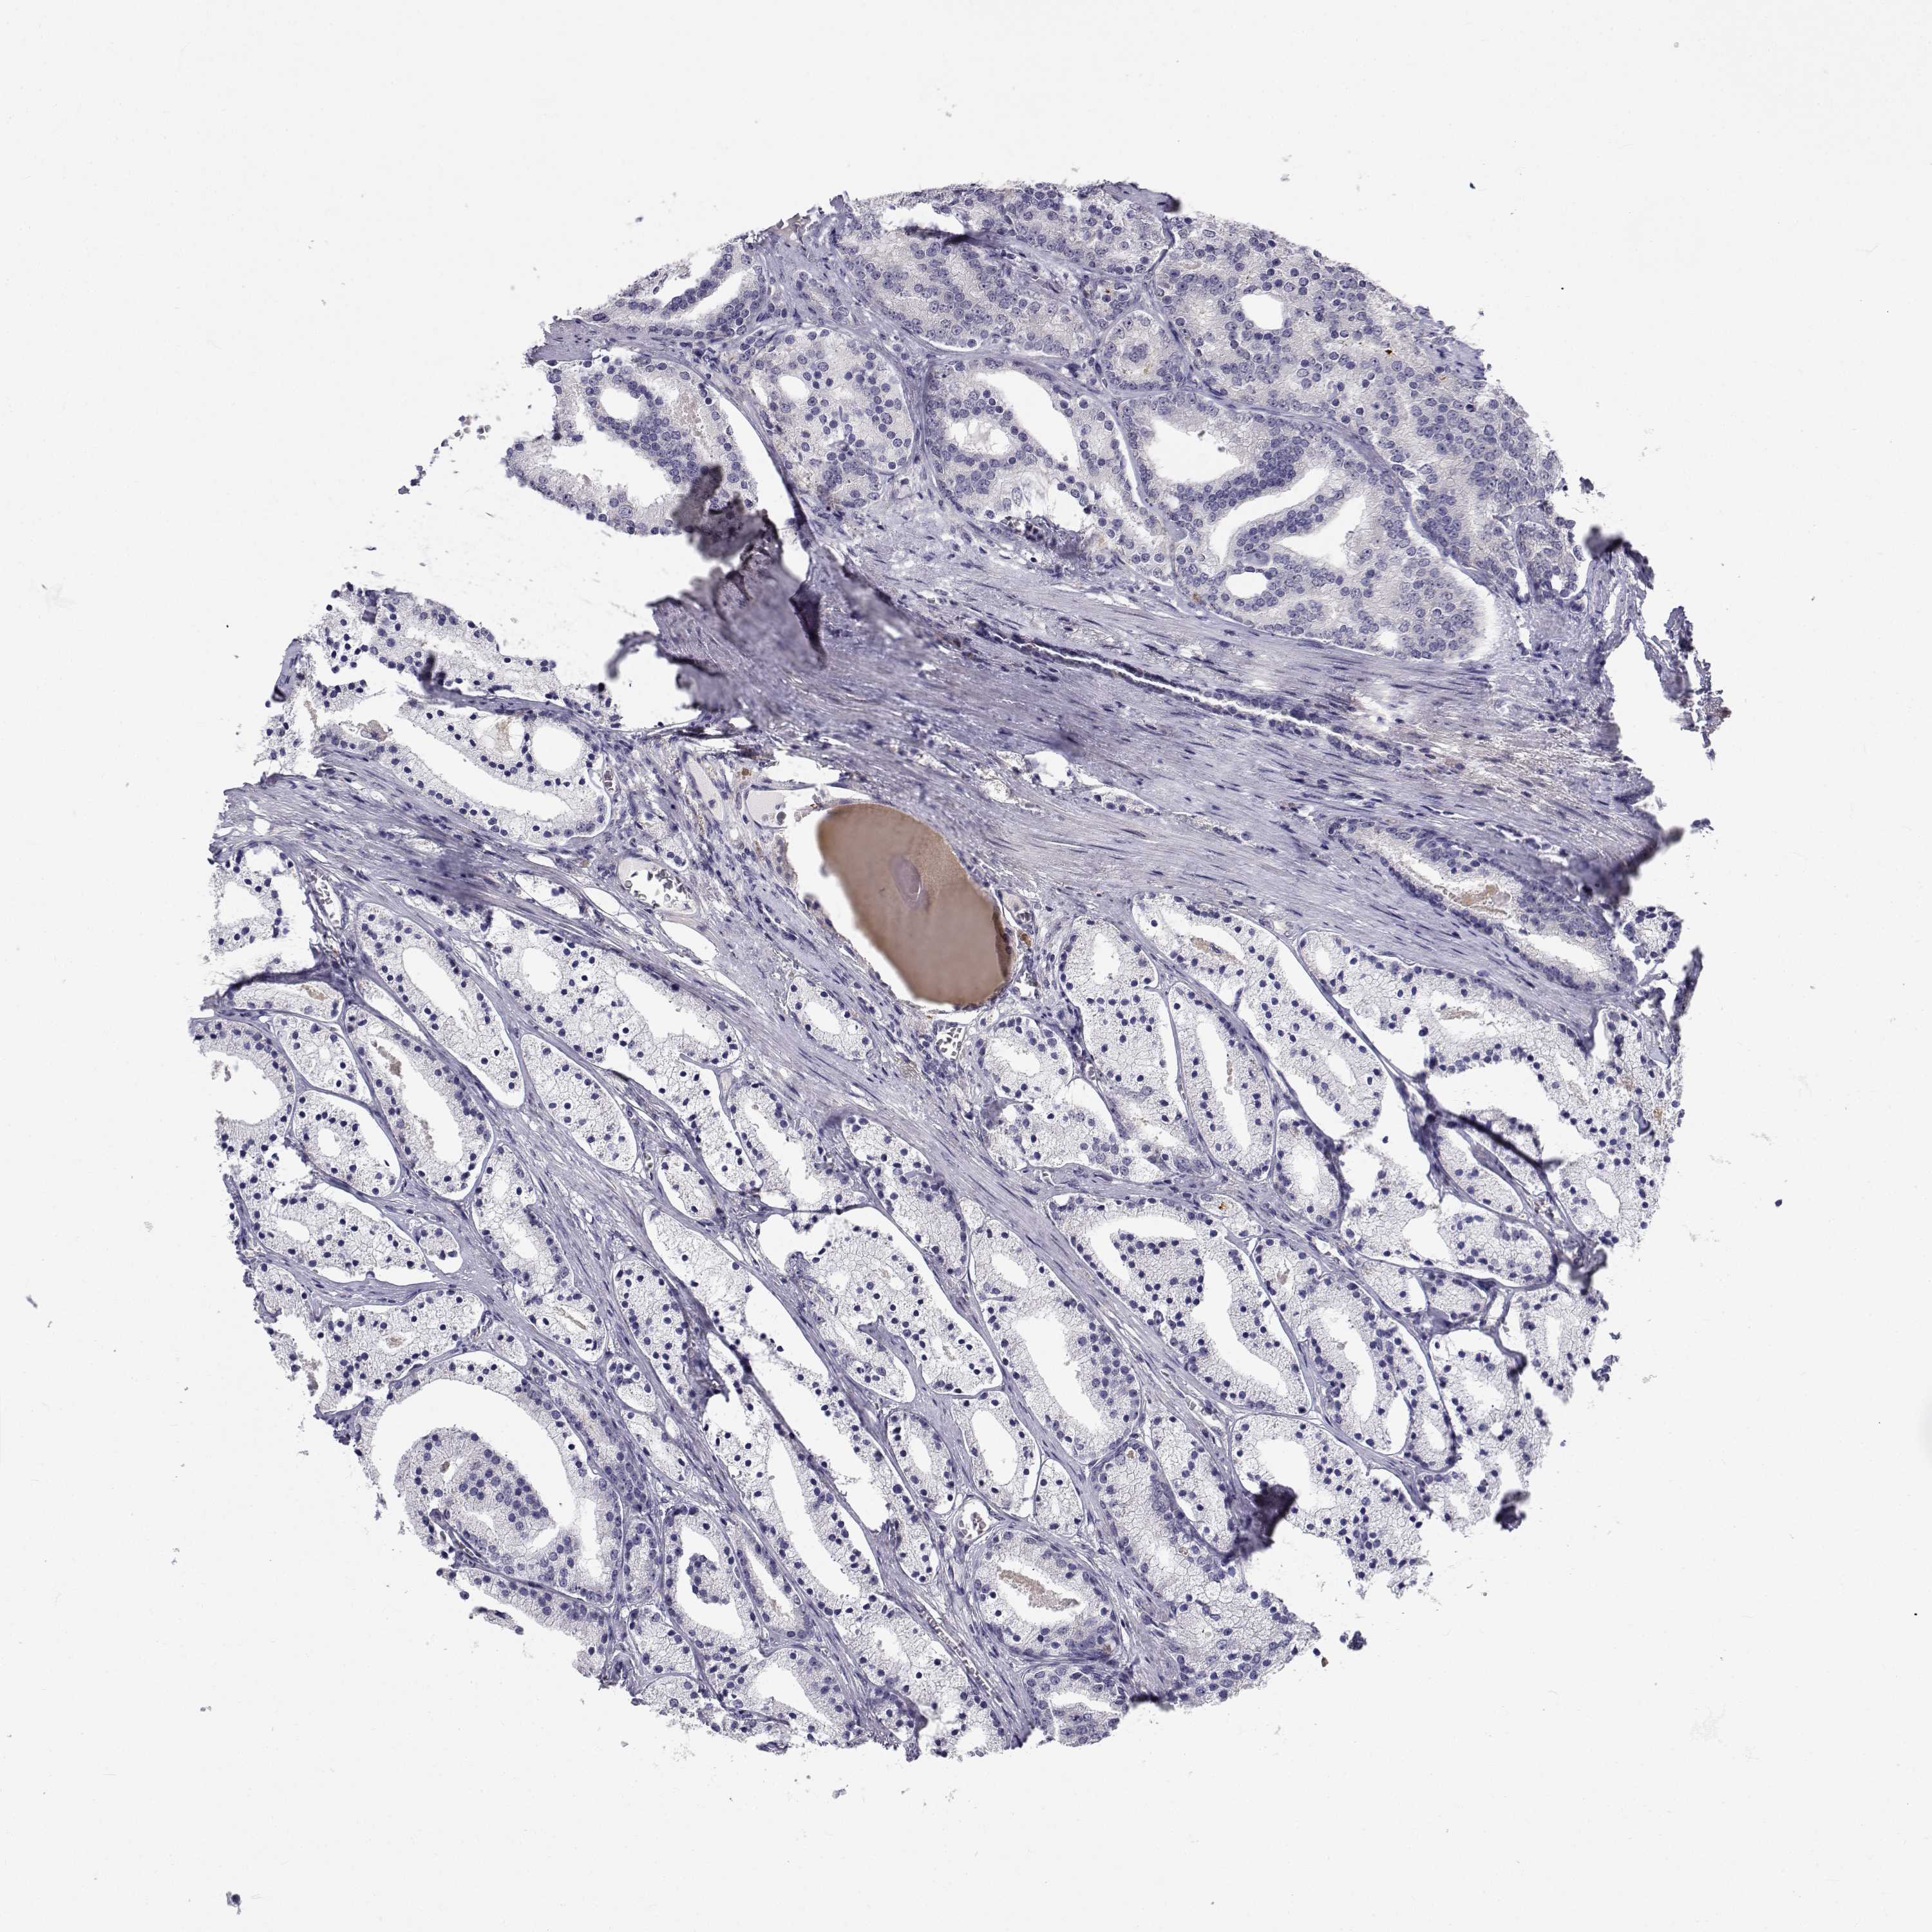

PROSTATE CANCER - Protein expressioni

A mouse-over function shows sample information and annotation data. Click on an image to view it in a full screen mode. Samples can be filtered based on level of antibody staining by selecting one or several of the following categories: high, medium, low and not detected. The assay and annotation is described here.

Antibody stainingi

Antibody staining in the annotated cell types in the current human tissue is reported as not detected, low, medium, or high, based on conventional immunohistochemistry profiling in selected tissues. This score is based on the combination of the staining intensity and fraction of stained cells.

Each image is clickable and will lead to virtual microscopy that enables deeper exploration of all samples and also displays staining intensity scores, fraction scores and subcellular localization as well as patient and tissue information for each sample.

Antibody CAB016249

Adenocarcinoma, NOS